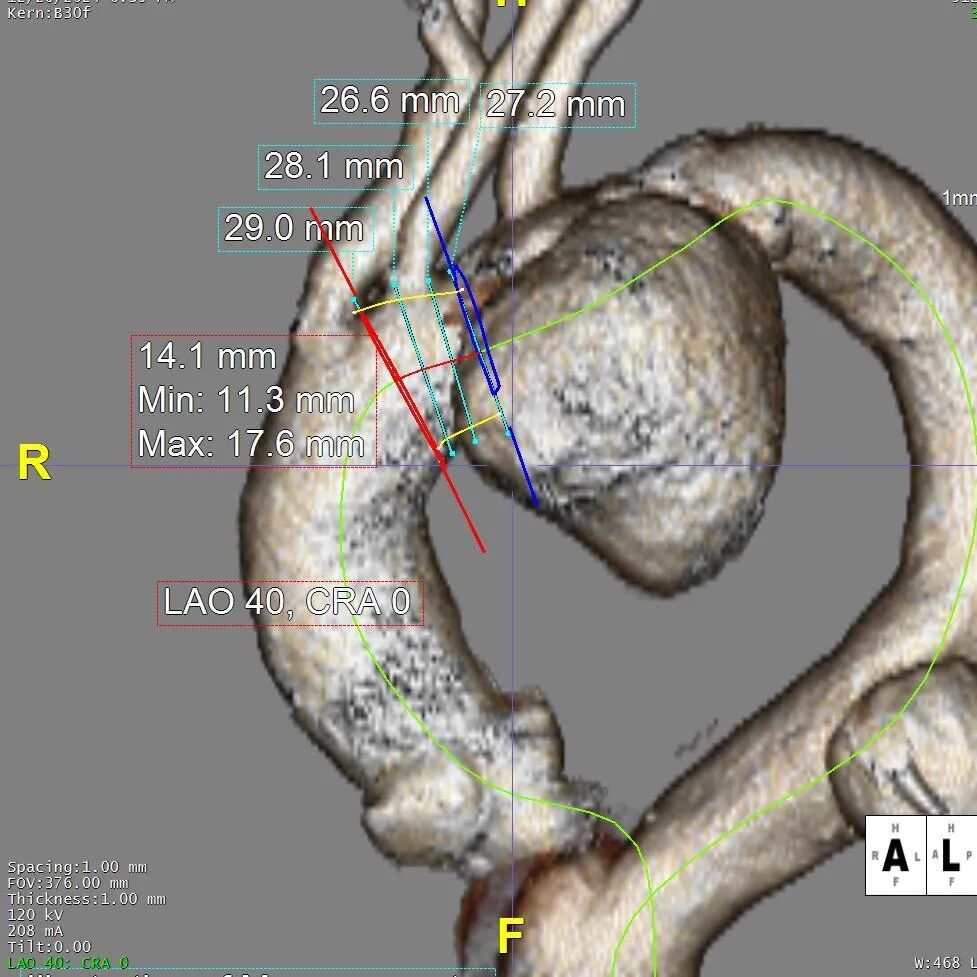

病变累及LCCA附近,小弯侧锚定区长度11mm,非常极限

考虑患者整体身体状况较差,选择腋动脉-左颈总动脉和腋动脉-左锁骨下动脉人工血管搭桥术,大支架锚定于INA后缘。由于病变累及至LCCA,INA后缘小弯侧锚定区极限11mm,为获得足够的健康锚定区,需要极其精准的定位,遂选择GORE® TAG® 可主动调控胸主动脉覆膜支架(以下简称“CADS”)。

1. CADS支架是分段式释放,在第一阶段半直径释放后,可以重新调整定位,对释放位置做更精准的控制;同时在进行第二阶段拉线释放时,支架从远端向近端全直径稳定释放,有效减少“风袋效应”,避免支架移位,精准定位。

2. CADS分阶段释放和完全释放的两个阶段均可以对小弯侧进行角度调控;改善支架近端与主动脉小弯侧的贴附,最大限度地避免“鸟嘴”发生,让支架更好贴合血管隔绝密封。

结合近远端血管直径及锚定区长度选择:近端戈尔CADS TGM343420+远端唯强DM-TC-3024200。